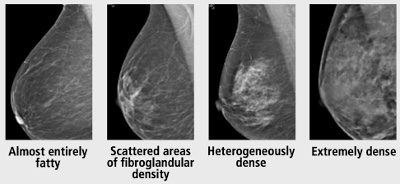

👉Density is categorized using a standardized system that was developed by the American College of Radiology that’s called the BI-RADS system.

👉We categorize breast density in four ways. One, breast can be completely fatty. That means it’s all fat. We don’t have any glandular tissue in the breast. Or scattered, meaning 25% to 50% density. Heterogeneously dense is 50% to 75% density, and extremely dense means there’s way more glandular tissue than there is fat.